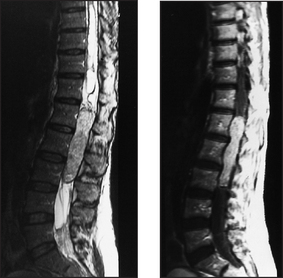

Some common examples of important diagnostic scans are shown in Figures 36.2–36.8 and 36.10.

Figure 36.10 Spinal cord tumour An MRI scan showing an intradural and partly extradural right C3 schwannoma. Axial (a) and coronal (b) T1-weighted images with gadolinium contrast. Note the large lobular tumour extending into the spinal canal and compressing the spinal cord (arrow). (Adam A. Grainger & Allison’s diagnostic radiology, 5th edn. Churchill Livingstone, 2008.) Churchill Livingstone